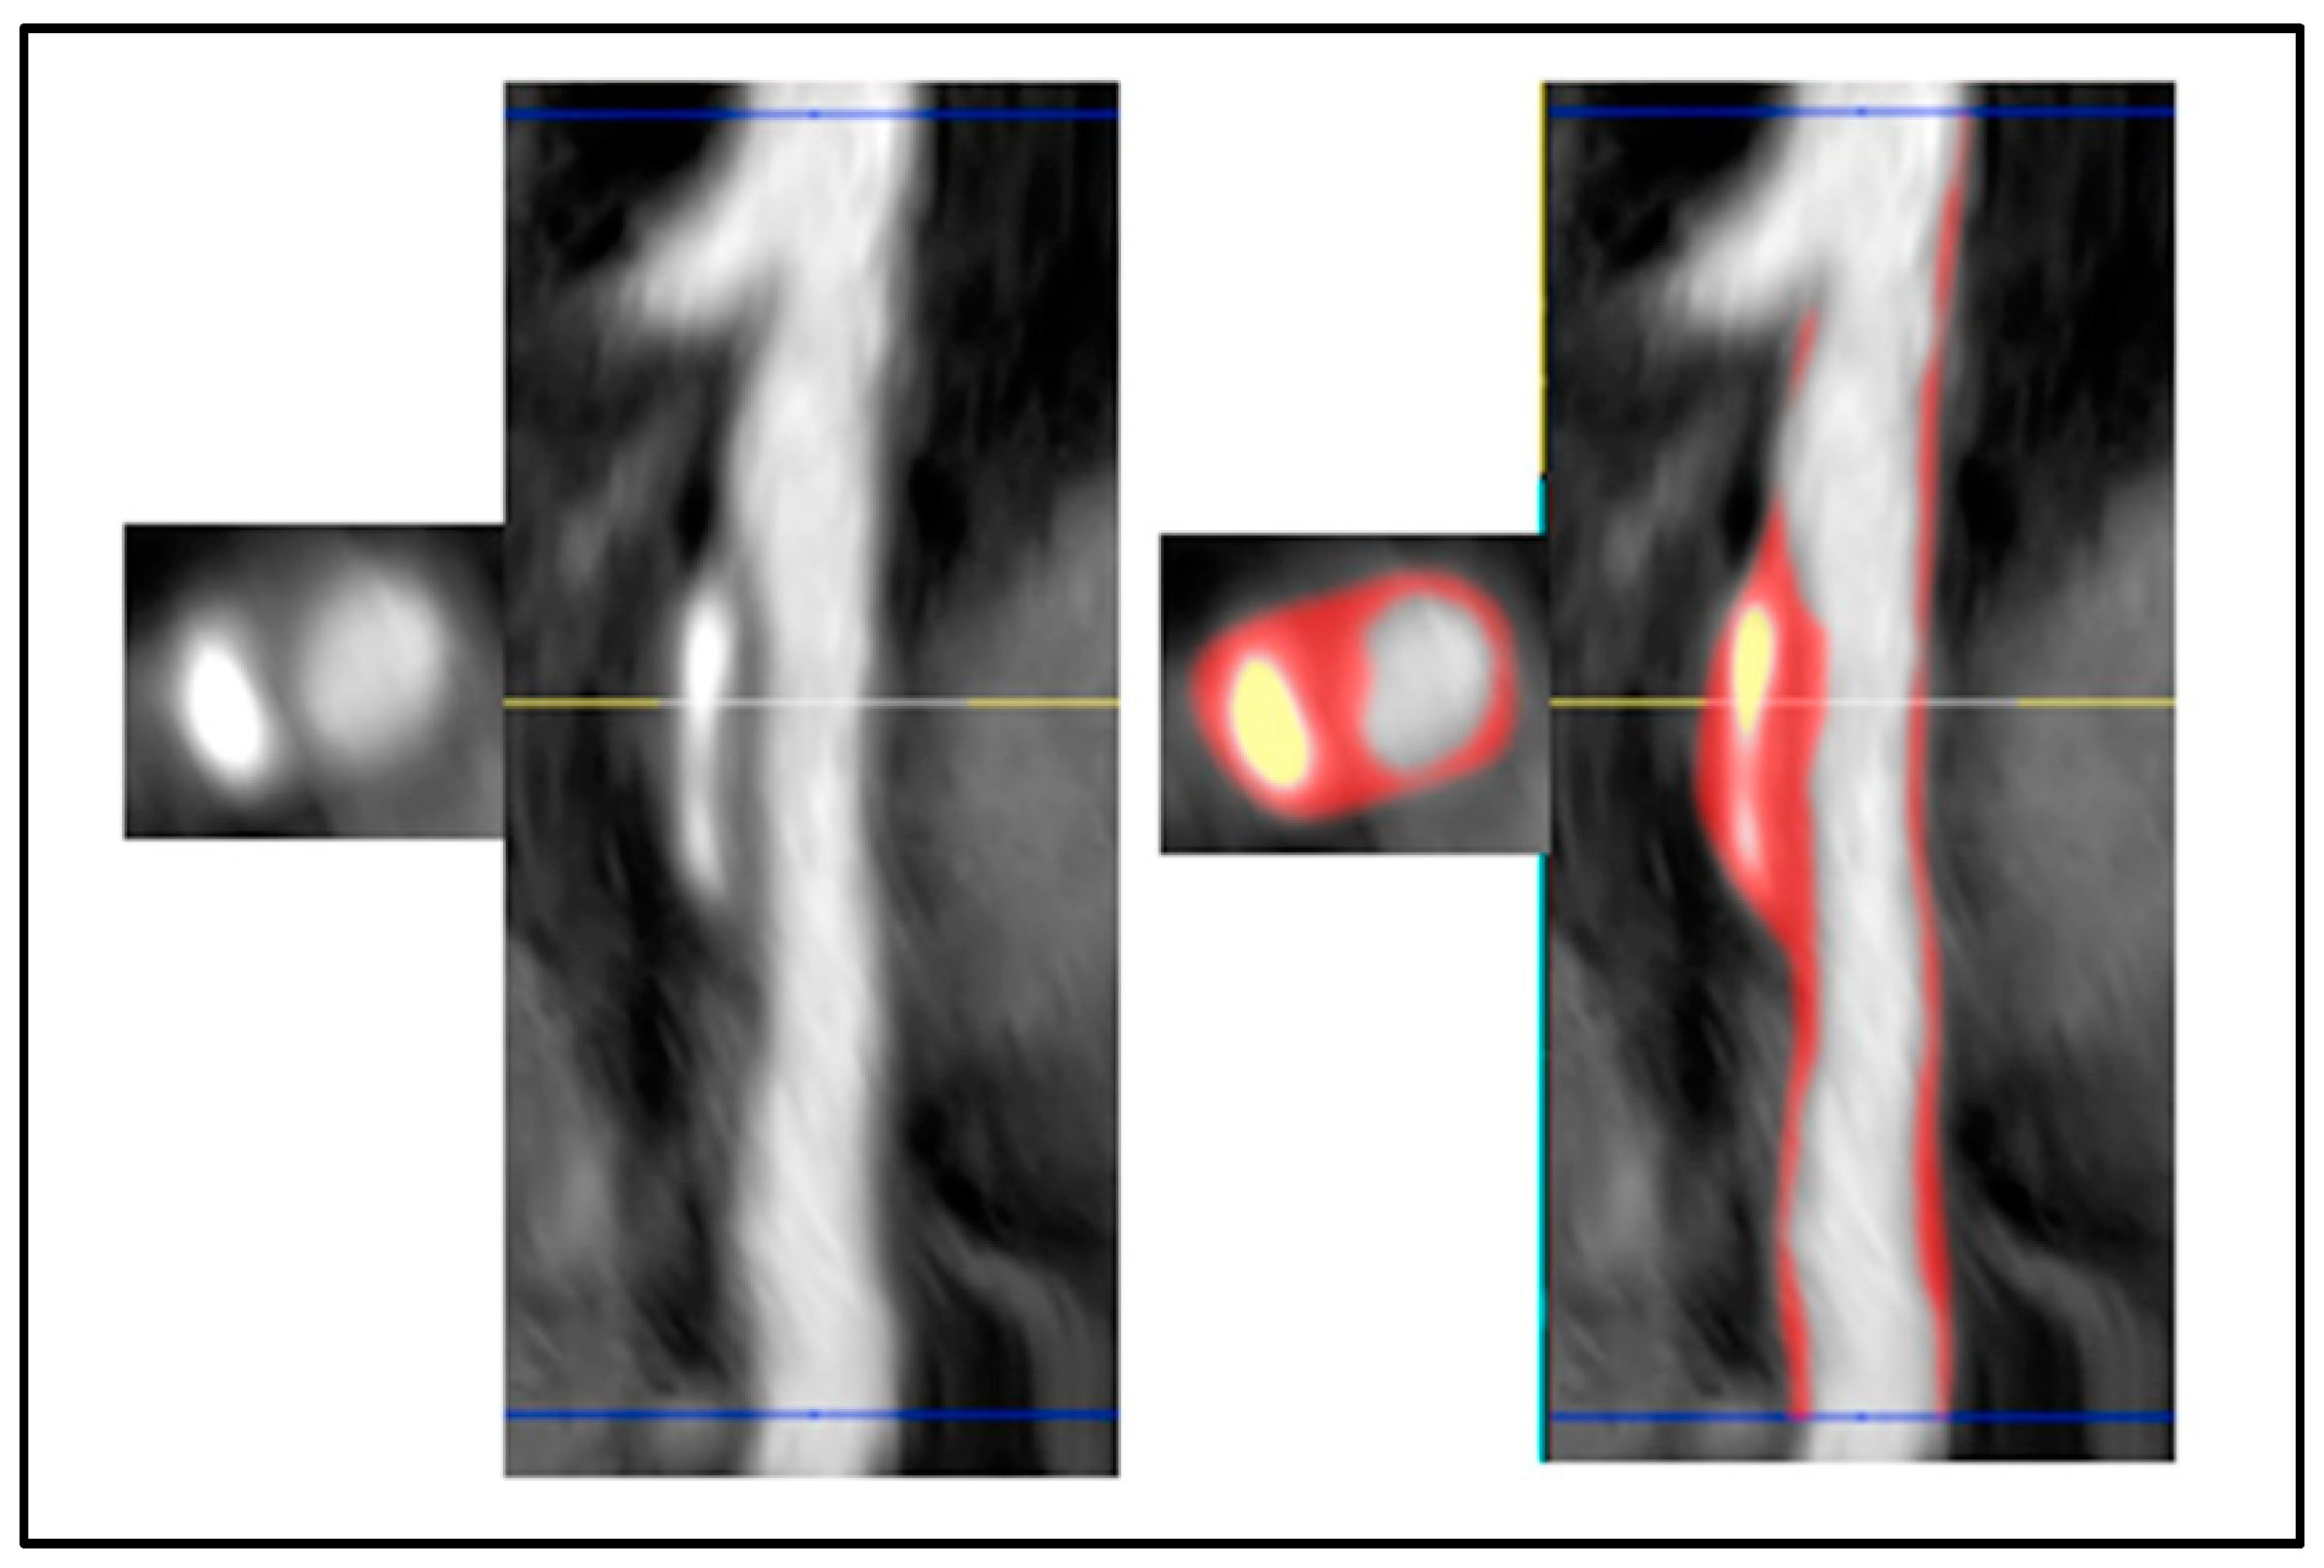

6. Cardiac Magnetic Resonance Imaging

6.1. Late Gadolinium Enhancement CMR

- Lanzafame, L.R.M.; Bucolo, G.M.; Muscogiuri, G.; Sironi, S.; Gaeta, M.; Ascenti, G.; Booz, C.; Vogl, T.J.; Blandino, A.; Mazziotti, S.; et al. Artificial Intelligence in Cardiovascular CT and MR Imaging. Life 2023, 13, 507. [Google Scholar] [CrossRef] [PubMed]